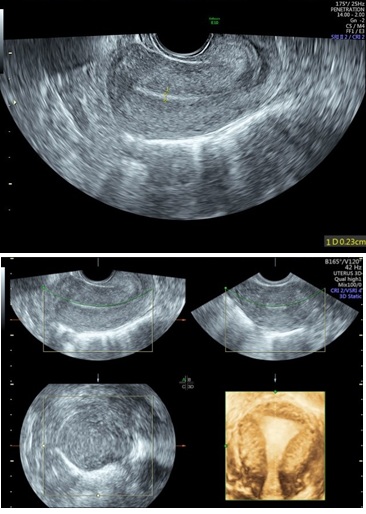

Figure 6: 2D & 3D USG showing Submucus Fibroid in Uterine Cavity.

Three-Dimensional Ultrasonography (3D USG) in comparison to hysteroscopy is less invasive, cheaper, easily accepted by most patients and does not require much training. In most cases an endometrial polyp can be differentiated from the submucous fibroid based on the imaging characteristics. The polyps are typically round in shape, smooth in outline, and are generally echogenic, compared to the endometrium or are isoechoic to it. The underlying endometrial-myometrial interface is preserved (Figure 5). Moreover the presence of a vascular pedicle has a positive predictive value of up to 81.3%. Fibroids are more inhomogeneous, hypoechoic, and there is a loss of endometrial-myometrial interface. The percentage of the intra cavitary portions of the submucous fibroids i.e., grade of submucous myoma can be assessed on 3D USG by the degree of distortion caused by it (Picture 6).